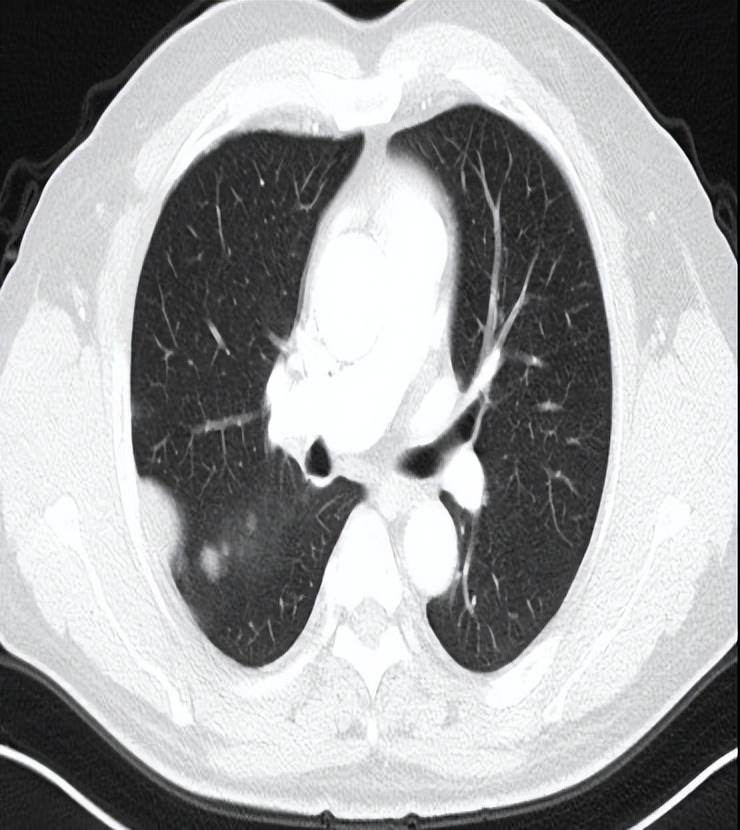

患者2020.6.16入院完善相关检查,评估疗效PD,考虑到二线化疗推荐吉西他滨,既往联合铂类也获得了不错的疗效,于2020-6-18至2020-9-21行二线化疗GP(吉西他滨1.8gD1、8+奈达铂45mgD1-3)方案化疗共4周期,后于2020-10-21行G-T1(吉西他滨1.8g)单药维持化疗。